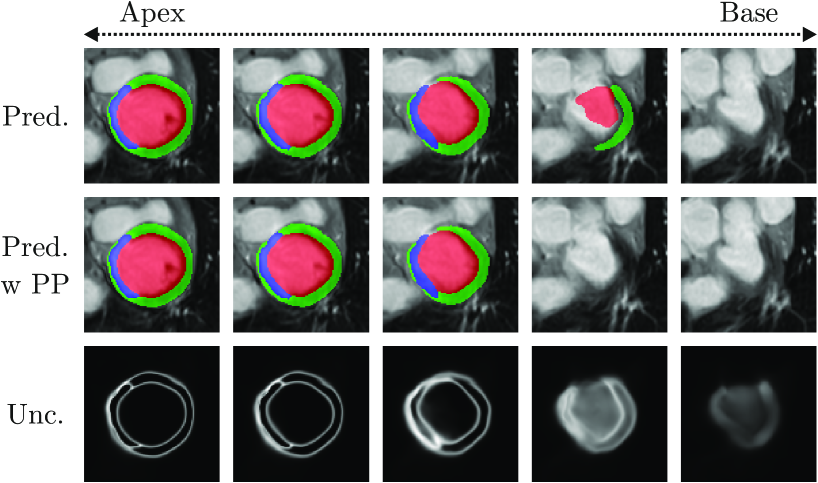

Refer to caption

Figure 3: Predictions of CaRe-CNN (row 1) are in some cases incomplete for the top-most slice towards the base of the left ventricle (col. 4). The model’s uncertainty is computed as the entropy of the softmax prediction (row 3), where bright values indicate a higher uncertainty. The highest uncertainty occurs in the incompletely labeled slice (col. 4). This motivates our post-processing (PP) where, in this case, the incomplete prediction is removed (row 2).

As can be observed in Fig. 3 (bottom row), after training on the data our CaRe-CNN remains ’uncertain’ about how far the heart should be segmented towards the base which may result in a top-most slice that is incompletely labeled. Even though such incomplete model predictions in themselves are not incorrect, we decided to implement a series of post-processing steps to obtain more consistent predictions that take anatomical constraints into account.

Next, we propose a top-most slice removal strategy, where we compare the remaining foreground volume of the topmost slice that contains foreground predictions to the foreground volume of its neighboring slice towards the hearts’ apex (i.e. the slice ’below’ the top-most slice). In case that the volume of the topmost slice is less than half the neighboring slice’s volume, the topmost slice is removed completely. An example is shown in Fig. 4 (col. 4).